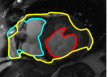

The problem above is a generalization of Horn & Schunck optical flow. Note that solving for the Horn & Schunck optical flow within each region separately does not lead to motions such that at the interface, they have equal normal components (see Figure 1), whereas the solution of (5) to be presented in subsequent sections does. Note that computing Horn & Schunck optical flow in each region requires boundary conditions (and typically they are chosen to be Neumann boundary conditions: and on ). Note that replacing these boundary conditions with the boundary constraint (6) does not specify a unique solution. Also, while Horn & Schunck optical flow computed on the whole domain naturally gives a globally smooth motion, which by default satisfies matching normals at the interface, this is not natural for the ventricles / myocardium, where different motions exist in the regions (see Figure 2), and the motions should not be smoothed across the regions.

![]() |

| image + boundary | next image | within region optical flow | our method |